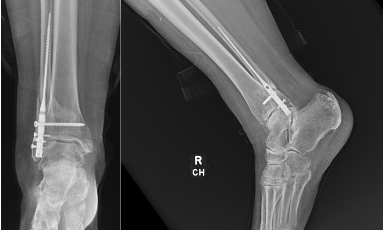

Fibular Intramedullary Fixation

In contrast to standard ORIF, fibular intramedullary fixation has become popular. With minimal soft tissue disruption, early weight-bearing, and similar outcomes compared to more traditional fixation, we can see the benefit for its use in geriatric fractures.13 Lin and colleagues compared intramedullary fixation versus traditional plate and screws in 32 geriatric patients with unstable fibula fractures. Overall, they found fewer complications in the intramedullary group, however, there were comparable functional outcomes and time to union between the groups. The study highlights if functional outcomes can remain similar with significantly decreased complications, then intramedullary fibular fixation is a valuable tool to consider.13 Appleton and associates specifically looked at intramedullary fibular fixation in geriatric ankle fracture patients with significant comorbidities such as diabetes mellitus. They found 85% of patients regained ankle range of motion within 90% of the uninjured side and maintenance of anatomic reduction in all but one patient.14 In patients with comorbidities, these implants can provide stable reduction while diminishing the soft tissue insult, and hence diminish complications compared to standard open approaches.

Carter and colleagues performed a cadaveric, biomechanical study examining fibular intramedullary fixation versus locking plate and lag screws on specimens with an average age of 86 years. The intramedullary group had higher mean torque to failure, greater angle of rotation to failure, and similar stiffness to standard plating and screws.15 With similar biomechanical properties to standard plating, the load-sharing properties of intramedullary nails can allow earlier weight-bearing and improved mobility for the geriatric population, which is vital. Fixation can usually be achieved with a long 3.5mm cortical screw, or more recently, commercial intramedullary nail implants.